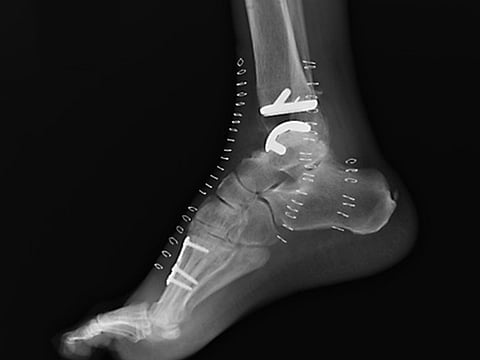

Ankle replacement surgery gains acceptance

Once disparaged as borderline quackery, the procedure — called ankle arthroplasty — is now used to treat arthritis

Courtesy of Duke Health